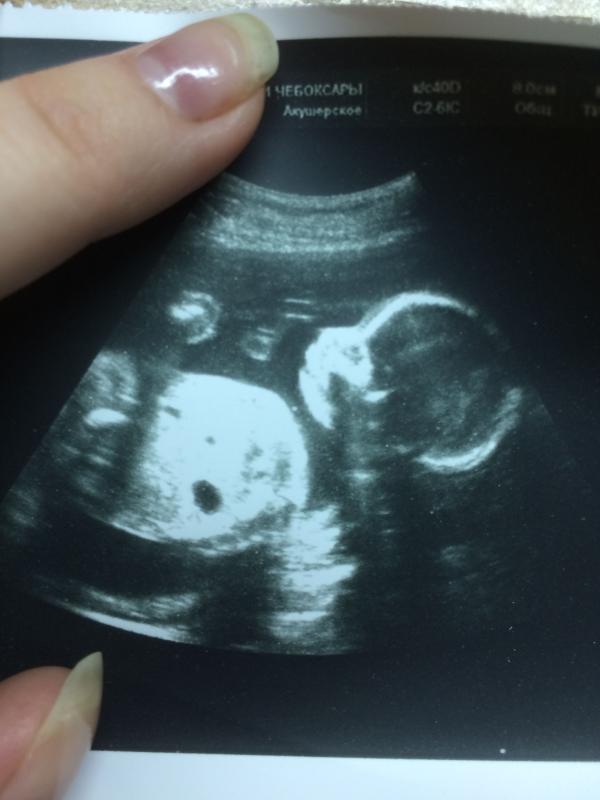

@mari_mammy, @zoya-kireeva, @nata.nata1998, @lesya.kiryanova00, @annee2, @dvina, @littlefox0503, @businkanika, @alina_y_malina, @gufo4ka1992, это апрельская фотка , сказали девочка, завтра иду на третье узи , вдруг скажут что мальчик🙈